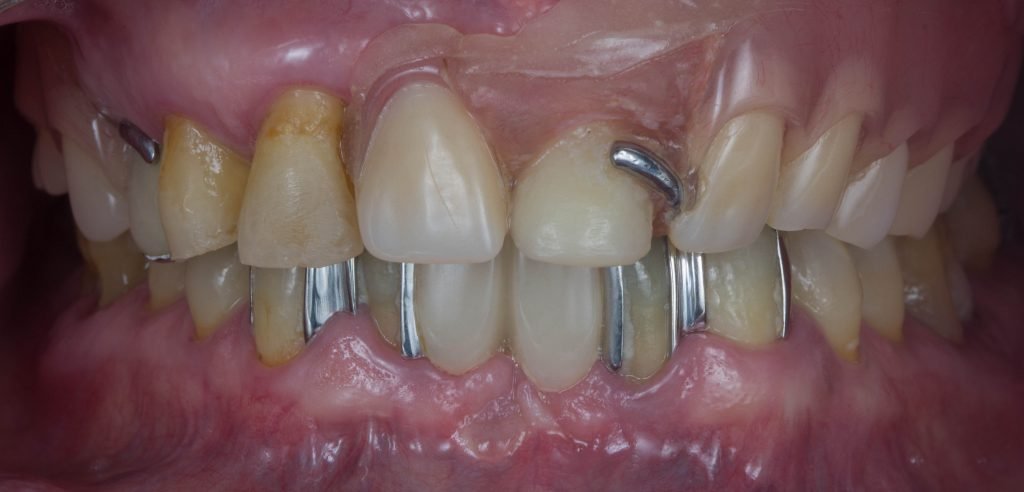

Punto Bajío Casos Clínicos Prótesis Fija sobre Implante unitario Inicio Provisional Final Prótesis Parcial Fija sobre 2 Implantes 2 Implantes Final Prótesis Bucal Removible Inicial Inicial Superior Inicial Inferior Rayos X Inicial Rayos X Inicial Frontal Final Final Superior Final Inferior Prótesis Parcial Fija/ Coronas de Circonio Sonrisa Inicial Foto Inicial Foto Inicial Inferior Foto Final Inferior Foto Final Sonrisa Final Prótesis Total Protesis Inmediatas 1 Protesis Inmediatas 2 Prótesis Removible/ Coronas Metal-Ceramica Carillas Incrustaciones Endodoncia